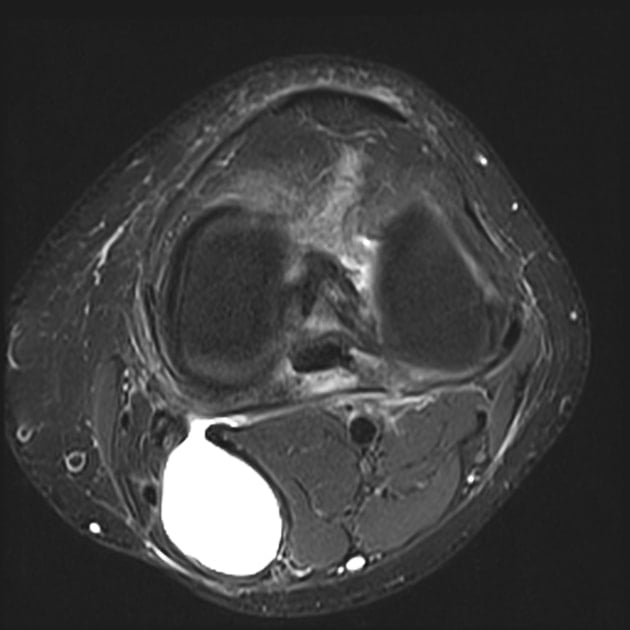

Baker Cyst Radiology Key